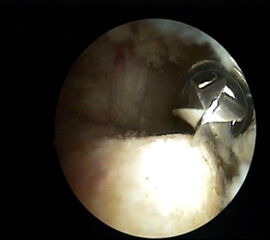

Abbildung 8, Video 3

Nach vollständiger Darstellung erfolgt die Resektion der Exostose mit einem Acromionizer von medial, wobei auch hier die geschlossene Seite des Arbeitsansatzes zum Schutz der Achillessehne nach dorsal ausgerichtet werden sollte. Verwendet werden können wahlweise Kugel-, Zapfen- oder Walzenansätze mit 3,5-5,5 mm Durchmesser. Ein kleinerer Durchmesser vereinfacht zwar das Handling im engen retrocalcanearen Raum, erfordert aber einen höheren zeitlichen Aufwand als die Verwendung einer höherkalibrigen Fräse. Der Knochenabrieb verstopft dünne Instrumente häufig und der Durchfluss der Spülflüssigkeit ist gering. Es hat sich bewährt, zwei verschiedene Größen bereitzuhalten und ggf. intraoperativ zu wechseln.